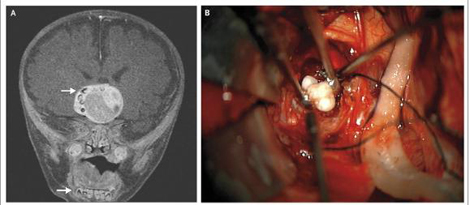

据《新英格兰医学杂志》(New England Journal of Medicine简称NEJM)网站2014年2月27日报道,纳林•贝内特•贝蒂(Narlin Bennet Beaty)博士和爱德华•安(Edward Ahn)博士撰文,介绍了他们在一名颅咽管瘤(Craniopharyngioma)小患者的肿瘤内发现了牙齿。详见图1照片。

图1 颅咽管瘤内发现了牙齿

NEJM报道的这名颅咽管瘤患者是刚出生只有4个月的一名男婴,分别在马里兰大学医疗中心(University of Maryland Medical Center)和约翰•霍普金斯儿童中心(Johns Hopkins Children's Center)均被诊断为颅咽管瘤。最终是在马里兰大学医疗中心接受了脑瘤摘除手术。肿瘤的摘除手术是由贝蒂博士和爱德华•安博士完成的。令医生感到惊讶的是,他们在婴儿脑瘤的摘除过程中发现,一名仅有4个月的婴儿,便开始长牙齿,而且是在最不寻常的和意想不到的地方——脑瘤中长了牙齿!

在过去,每当发现科学异常现象后,由于常常不明原因,很多时候未能及时治疗。贝蒂博士说:“在现代外科时代之前,这个患有颅咽管瘤的孩子就不可能幸存下来。但是,现在不同了,他的手术做得非常好,从整体来看,这是一个在孩子大脑中心的大肿瘤。”在脑瘤中发现的牙齿被送到实验室进行进一步的研究,因为这些类型的组织样本有时在未来几年是有用的。更多信息请浏览:Narlin Bennet Beaty, Edward Ahn. Adamantinomatous Craniopharyngioma Containing Teeth. New England Journal of Medicine,2014; 370: 860. February 27, 2014. DOI: 10.1056/NEJMicm1308260